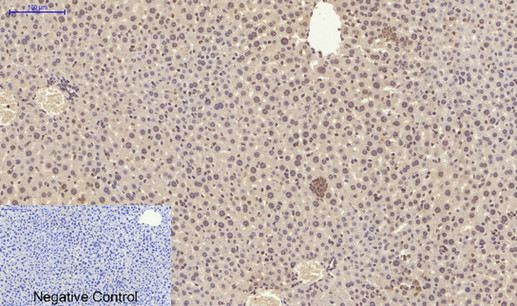

ARG66190 anti-Smad 2 antibody IHC-P image

Immunohistochemistry: Paraffin-embedded Rat spleen tissue stained with ARG66190 anti-Smad 2 antibody at 1:200 dilution (4°C, overnight). Antigen Retrieval: Boil tissue section in Sodium citrate buffer (pH 6.0) for 20 min.

Negative control was used by secondary antibody only.